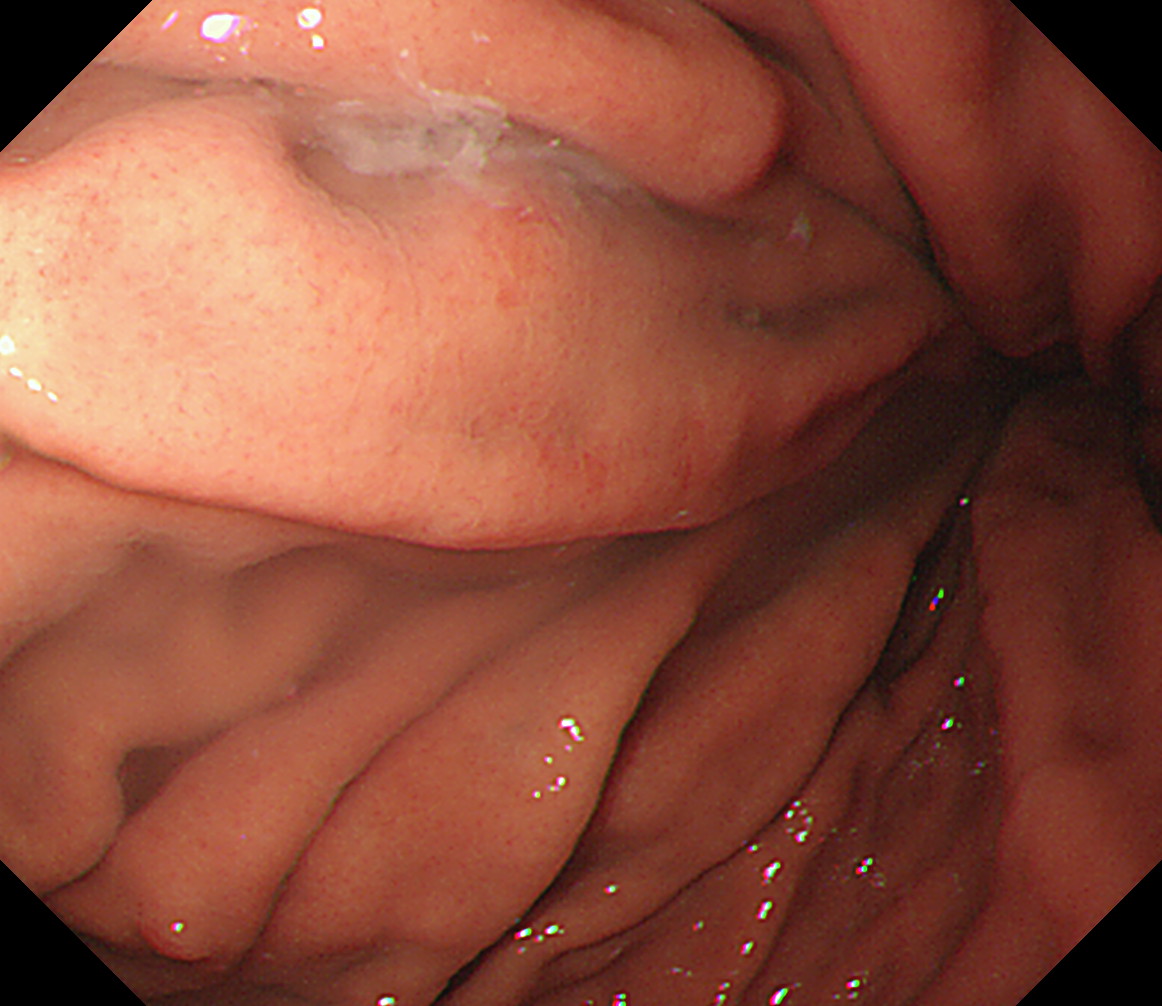

22 噴門部小弯 [J反転]に戻る

胃体上部小弯と近い画像

噴門部小弯[J反転]

23 胃角部大弯 以下ずっと[見下ろし]でくるくる反時計方向に回しながら引き上げていく

萎縮境界の観察なども行います

胃角部大弯